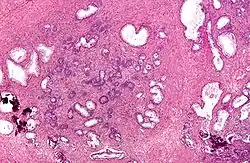

![]() Micrograph of a transurethral resection of the prostate (TURP) specimen, showing BPH (nodular hyperplasia of the prostate) – left-of-center in image. H&E stain. | |